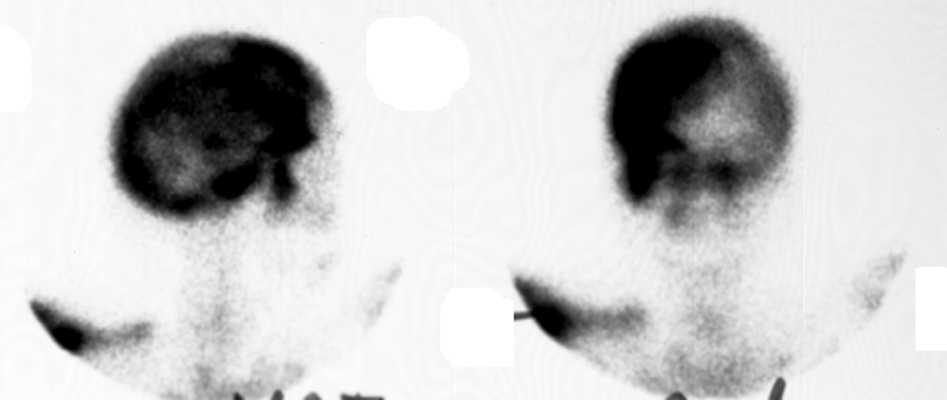

Diagnosis:Paget's Disease Discussion:Plain film of the skull reveals a large mottled area of radiolucency with small areas of increased density within it. The MR image of the skull reveals a thickened, enlarged cranium with increase in the marrow space. Two bone scan images also reveal increased activity in the skull, more localized to one side, characteristic to the localized disease seen in Paget's. This is classic cranial involvement of Paget's. In the cranium, bone sclerosis may produce circular radiodense lesions in one area, whereas osteoporosis circumscripta is noted elsewhere. In the skull, the common region of involvement is the cranial vault. The osteolytic phase is called osteoporosis circumscripta and appears as multiple geographic, well-demarcated regions of bone resorption that may be mistaken for metastases. Focal radiodensities occur as pagetoid bone is formed. In the quiescent phase, there is a radiodense cotton-wool appearance with a thickened vault. References: